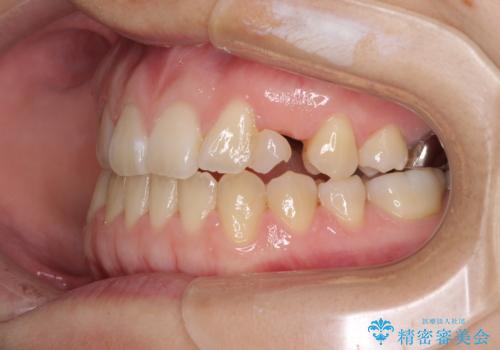

受け口で開咬を急速拡大装置とインビザラインで改善 欠損部分はインプラントにて補綴治療

- 前歯の開咬と、受け口による咬み合わせの悪さを気にして来院された患者様です。

左上は後続永久歯の欠損によりスペースがあり、矯正治療と並行してインプラントあるいはブリッジによる補綴治療が必要な状況でした。

上顎歯列が狭窄していたため、急速拡大装置により上顎骨を側方に拡大し、その後インビザラインにて矯正治療を行うこととしました。

矯正治療が終わるタイミングに合わせてインプラントの埋入を行っていたので、矯正治療を終了すると同時にセラミック補綴治療を行えました。

インビザラインの装着時間が不十分であったので、治療期間は長期間となりました。